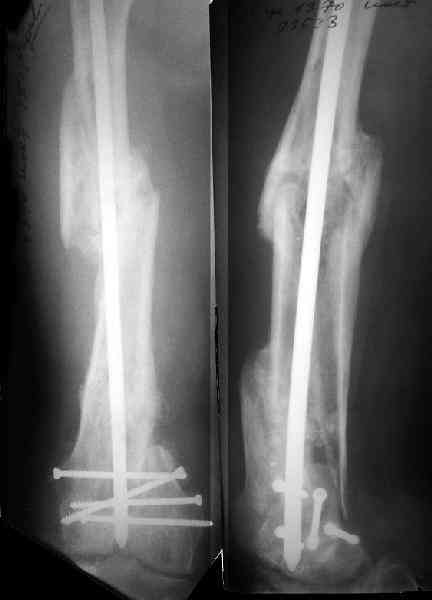

По прямой проекции неплохо. Что за стержень?

Антеградный остеосинтез при дистальных переломах бедра мы применяем давно, этот материал обобщен в канд. диссертации Александра Виноградского.

Ободранные рашпилем до 6 мм в диаметре спонгиозные винты 6,5 мм тоже доводилось использовать.

Предприятие ЦИТО выпускает доработанные нами гвозди, которые хорошо годятся для дистальных переломов, да и недороги. Можно вводть в дистальное овальное отверстие 3 винта, которые заклинивают друг друга.

Большеберцовые стержни отлично выполняют роль ретроградных бедренных. Конечно, которые не 9, а 12 мм в диаметре.

Примеры приложены.

И вообще мне кажется, что представленный ОС не допустим:1. стержень в суставе,2. неправильная длинна винтов, 3. ось конечности неправильная, 4. циркулярная гипсовая повязка после ОС?????

-1. стержень в суставе,

Это не критично, в межмышелковой борозде,не на опроной поверхности, выступает из субхондральной кости, не факт что из хряща.Про надколенник Александр Николаевич уже писал.

-2. неправильная длинна винтов,

и толщина тоже. При такой длине хочется помощнее.

-3. ось конечности неправильная,

Вполне прилично. Если в боковой проекции рекувации нет. Где кстати боковая, хочется спросить у постмейкера.

- 4. циркулярная гипсовая повязка после ОС?????

К сожалению, автор умалчивает. Думается, что в данном случае можно и без гипса.

-Почему было не использовать накостный ОС?

Доля ответа есть в названии города.

-Или при отсутствии МК не вести больного консервативно?

Если в боковой проекции все не менее достойно, и винты в отверстиях, это метод выбора.

-А отвечая на поставленный вопрос: можно, но зачем?

Затем, что результаты как минимум не хуже, чем при использовании глубокоспециализированных DFN. Другое дело, что найти толстый тибиальный гвоздь больше 11м не всегда просто. В показаном примере он бы не подошел. Трочал бы сильнее из колена или при полном погружении отверстия пролетели бы проксимальнее перелома. Он показан больше для нижней трети, чем для области метафиза. Да и желательно чтобы винты толстые были, толще чем для тибии.

Приносим извенения за недостаток информации. Выкладываю все снимки. Стержень фирмы НПО ДЕОСТ(г.Пущино-на-оке)